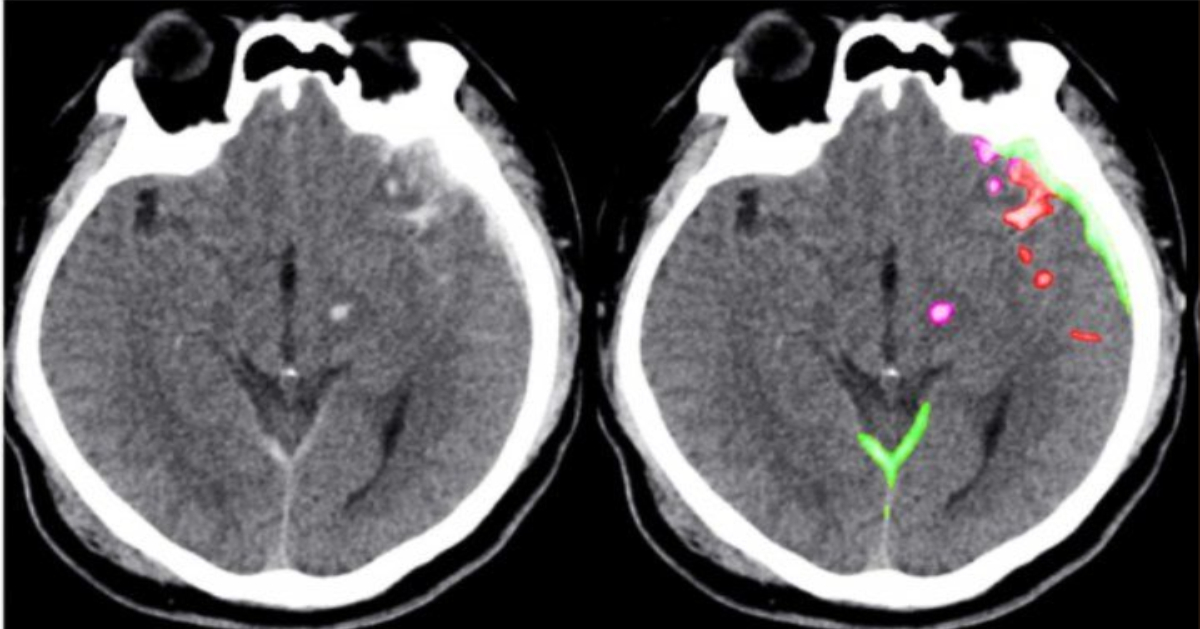

The algorithm the team developed took just one second to determine whether an entire head scan contained any signs of hemorrhage. It also traced the detailed outlines of the abnormalities it found – demonstrating their location within the brain’s 3D structure. Some spots may be on the order of 100 pixels in size, in a 3D stack of images containing over a million of them, and even expert radiologists sometimes miss them, with potentially grave consequences.

The algorithm found some small abnormalities that the experts missed. It also noted their location within the brain, and classified them according to subtype, information that physicians need to determine the best treatment. And the algorithm provided all of this information with an acceptable level of false positives – minimizing the amount of time that physicians would need to spend reviewing its results.